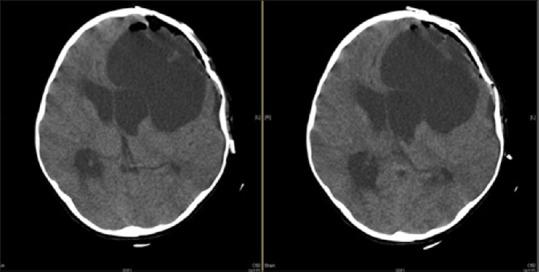

Primary Giant Cerebral Hydatid Cyst in an 8-year-old Girl.

Echinococcosis, also called hydatid disease, is a parasitic disease that passes from animals to humans. Literature reports suggest very rare cases of cerebral hydatid cysts. Brain involvement with hydatid disease occurs in 1%-2% of all infections. In this report, we aim to emphasize the presentation of such an isolated primary cerebral hydatid cyst, discuss its radiological features, Emergency department management, inpatient medical management, referral to neurosurgery, consequent operative procedures, postoperative care, and outcome.